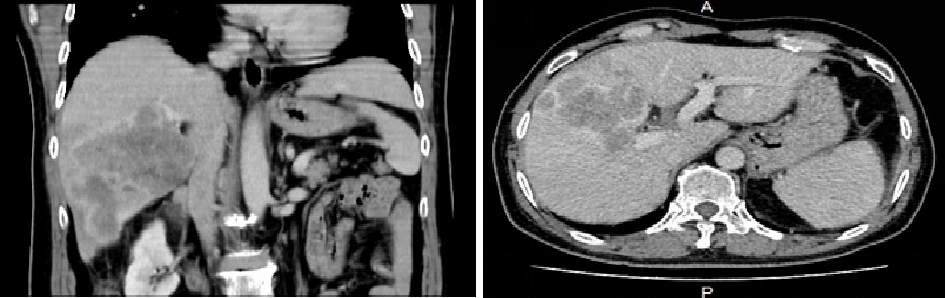

辅助检查:上腹部CT增强扫描2021-05-28诊断意见:1、肝右叶占位考虑原发性肝癌,建议穿刺活检。2、肝内多发低密度影,考虑转移。

系统治疗6周期后影像复查:

上腹部CT增强扫描2021-11-29诊断意见:1、肝癌并肝内多发转移治疗后改变,病灶较前缩小,其内见多发碘油沉积。建议定期复查。